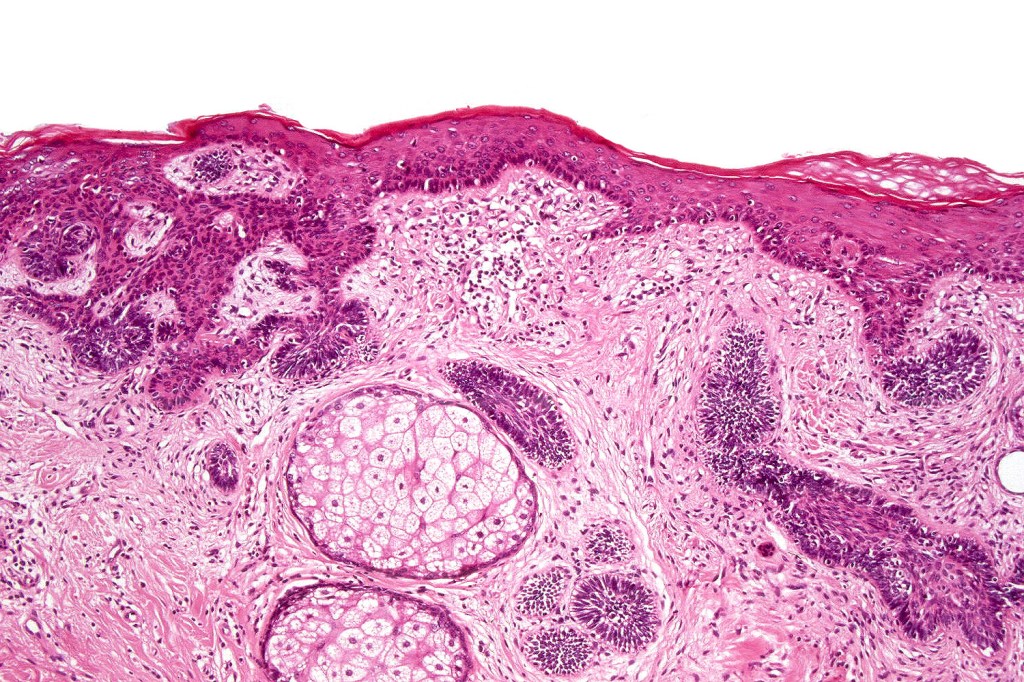

•Sharply circumscribed, unencapsulated nodule in deep dermis +/- subcutaneous fat or deeper (trichoepithelioma is much more superficial)

•Although many authors state that an epidermal origin/connection is not a feature of trichoblastoma, my own experience is that this can often be present particularly in those examples where a superficial dermal component is present in addition to the deep dermal/subcutaneous element

•Variably sized but generally large, basophilic tumor nodules composed of small uniform basaloid cells with minimal cytoplasm

•Peripheral palisading but no retraction artifact or stromal mucin deposition

•Variable keratocysts

•A rich fibromyxoid mesenchymal stroma with variable papillary mesenchymal bodies (sometimes these are absent)